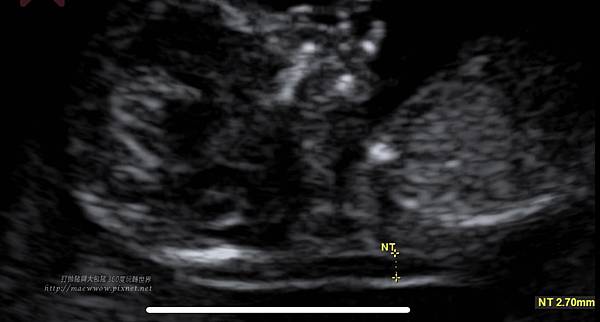

超音波檢查過程中,頸部透明帶2.7,(頸部透明帶的標準值為2.5或3mm以下),勉強在合格邊緣

媽媽自己聽到鬆了一口氣,但醫生卻說照不到小孩鼻骨,這樣的風險會變高。

原來,近年來,唐氏症篩檢新進展是在懷孕初期以胎兒的後頸部透明帶及鼻樑骨超音波篩檢,來預測胎兒罹患唐氏症機率的高低。

「英國倫敦皇室學院附設醫院胎兒研究中心醫師研究發現,在篩檢期間唐氏兒中有73%鼻樑骨並未發育完成;相對的,染色體正常的胎兒則只有0.5%缺乏鼻樑骨。胎兒鼻樑骨缺乏,則胎兒可能為唐氏症的機率將是正常胎兒的近一百五十倍。進一步分析發現,在懷孕第11至第14週合併產婦年齡,胎兒後頸部透明帶厚度(NT)作唐氏症篩檢,其偵測率為75%;若合併前二項指標,再加上胎兒鼻樑骨偵測(NB),則產前唐氏症的偵測率將可提高至85%,而偽陽性則由5%降至1%。」--節錄至蕭勝文醫師 / 鄭博仁副教授,後頸部透明帶及鼻樑骨超音波篩檢,第34期長庚婦產通訊

即使如此,等待的日子仍舊難熬,期間不斷google偽陽性的機率,別人翻盤的案例,把超音波的照片放大最大,想要找尋那一丁丁的小鼻骨的蹤跡,但網路上分享鼻骨的案例真的比較少,那一周上班哭、回家哭,每一兩個小時就會去刷一次禾馨的APP,看檢驗報告出來沒。

這是我個人經驗分享,附上個mini鼻骨寶,希望我的mini鼻骨寶翻案的案例可以給大家做個參考。